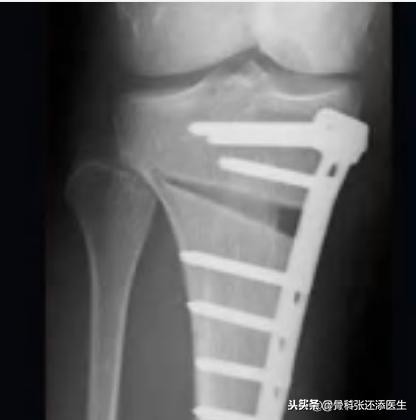

截骨手术

膝关节周围截骨术(HTO):这个手术主要矫正力线的不正常。就像桌子,一边高一边低,将低的那边踮高固定,桌子就重回稳定状态了。膝关节也一样,膝关节不平衡,导致力线不正常(髋关节到膝关节再到踝关节应该能以一条直线贯通,称为力线),从而加重磨损退变和疼痛产生。